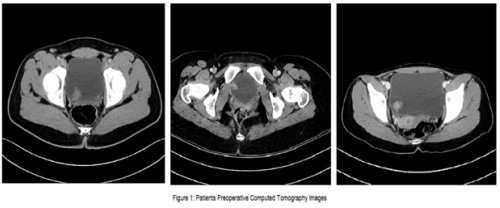

Ender Cem Bulut, Mahmut Uğurlu, Mustafa Kaba

Double-J (DJ) stents are essential tools in various urological

procedures []. With the increasing frequency of DJ stent use,

stent-related morbidities have become more prevalent. In the

short term, complications such as pain, irritation, infection, and

hematuria may occur. In the long term, serious complications

including encrustation, urolithiasis, stent migration, fracture,

renal damage, and even death have been reported []. DJ

stents may require removal through extracorporeal shock

wave lithotripsy (ESWL), cystolithotripsy, laser lithotripsy,

percutaneous nephrolithotomy (PNL), open surgery, or

combinations of these approaches [].

Cerebral palsy (CP) is a neurological disorder affecting

motor function and is frequently associated with urological

complications, particularly lower urinary tract dysfunction [].

The management of urolithiasis in patients with CP is often

challenging due to physical disabilities, anatomical variations,

and accompanying comorbidities [].

Fractured DJ stents are rare clinical occurrences. In this case

report, we present the endourological management and singlesession

removal of a severely encrusted DJ stent that remained

in situ for approximately 2.5 years.